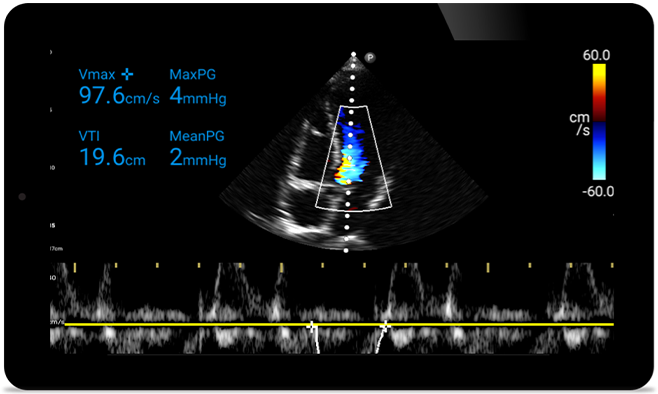

Actúe más rápido para proteger el corazón de sus pacientes

Cuando los segundos cuentan, el ultrasonido portátil puede marcar la diferencia. Lumify puede proporcionar las imágenes de alta definición que requiere cuando y donde las necesite.